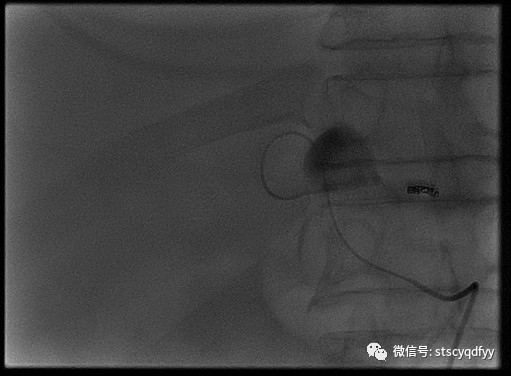

我院领导对患者病情高度重视,由医教科主持组织全院多学科会诊(MDT)讨论患者病情,经讨论决定将患者转入介入科实施经皮肝动脉造影+栓塞术,并充分做好术前相关准备工作。手术邀请汕头市中心医院血管介入科主任马洺远前来指导,由我院介入科副主任郑力文施行。术中造影显示肝左动脉分支远端见瘤状扩张,直径约2cm,见造影剂喷射,予弹簧圈栓塞并注入少量聚乙烯醇泡沫栓塞颗粒(PVA-300),复查造影动脉瘤未见显影,未见造影剂喷射外渗,术后血压快速回升至103mmHg/79mmHg。术程顺利,术后患者安返病房。